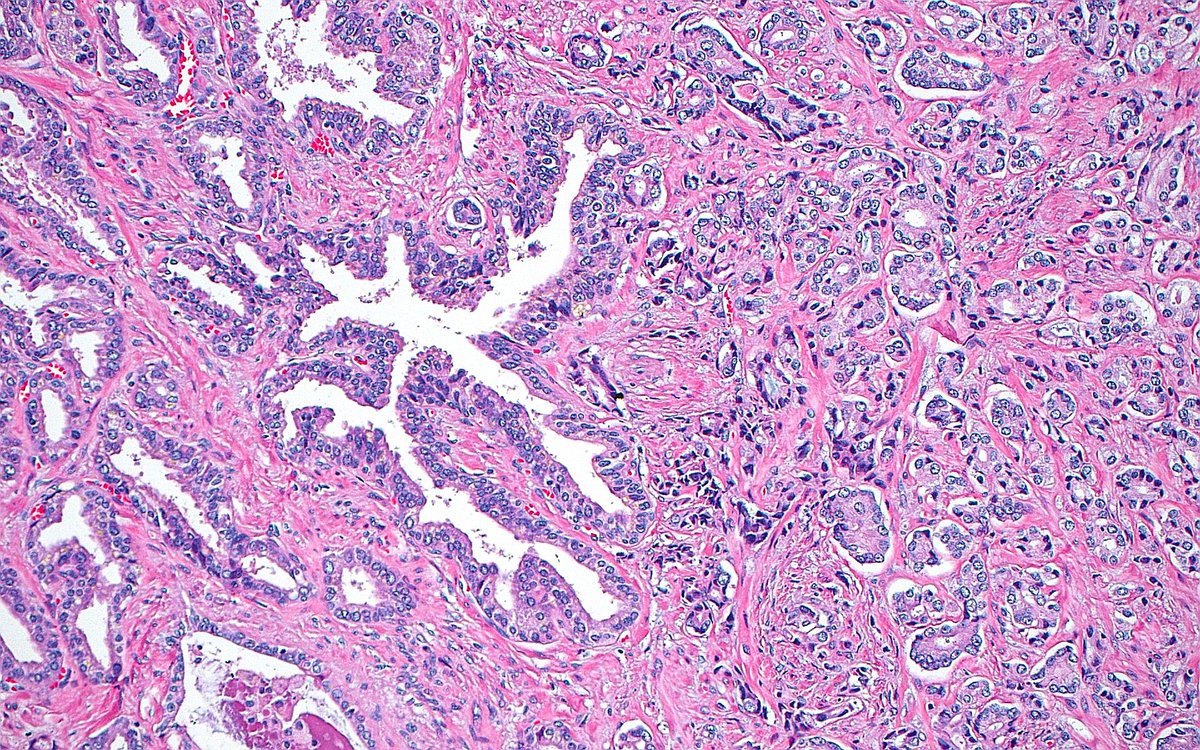

🔬 Seminal Vesicle Invasion ~ Prostate cancer glands (right half of image) and benign seminal vesicle epithelium (left half of image) ~ #GUpath #Pathology #Prostate